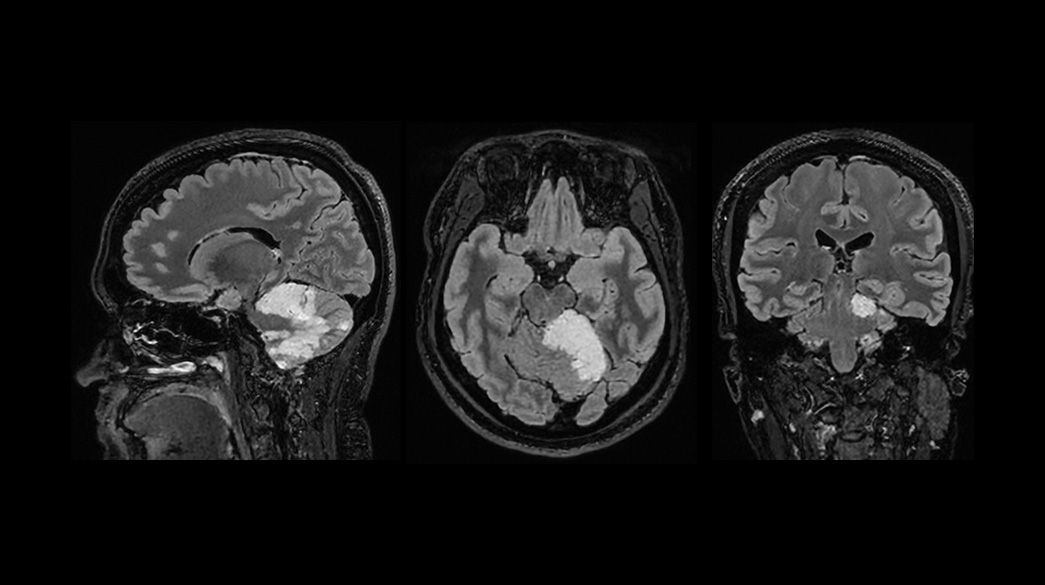

Oncology MR imaging techniques to capture anatomical and morphological data with robust tissue contrast, motion-insensitive and high temporal and spatial resolution for oncological assessment.

Oncological MRI imaging applications

Diagnostic confidence and consistency